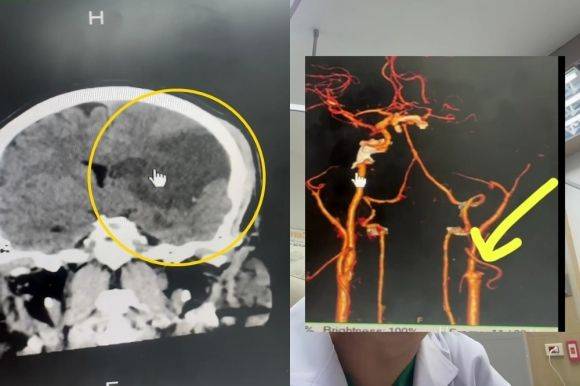

이 남성은 전날 저녁 식사 후 목이 뻐근해 아내에게 목 마사지를 받았고, 이후 이상 증세가 나타나 병원을 찾았다. 뇌 스캔 검사 결과, 뇌 상당 부분이 괴사 한 것으로 확인됐다. 추가 정밀검사 결과 경동맥이 끊어져 뇌로 들어가는 혈류가 차단된 상태였다.

컴퓨터 단층 촬영(CT)을 통해 검사한 결과 최소 8시간 이상 뇌의 혈액 순환이 제대로 이뤄지지 않은 것으로 추정됐다.